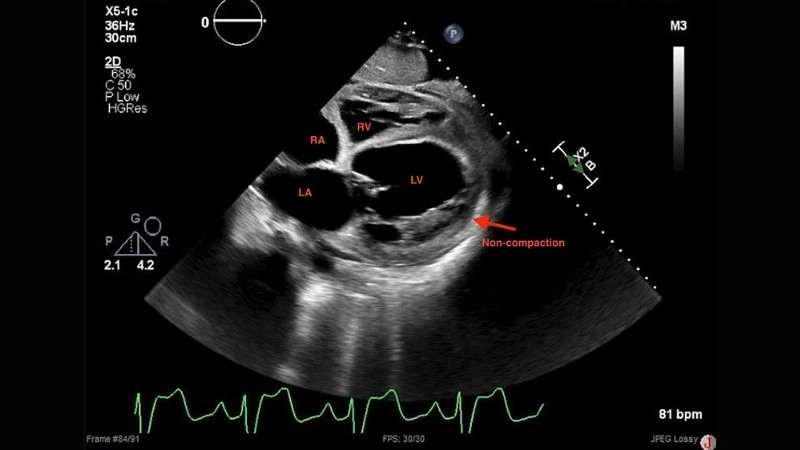

Images visual examples of Left Ventricular Non-compaction Cardiomyopathy

This abnormal structure weakens heart function, disrupts blood circulation, and can lead to life-threatening complications if not diagnosed early.